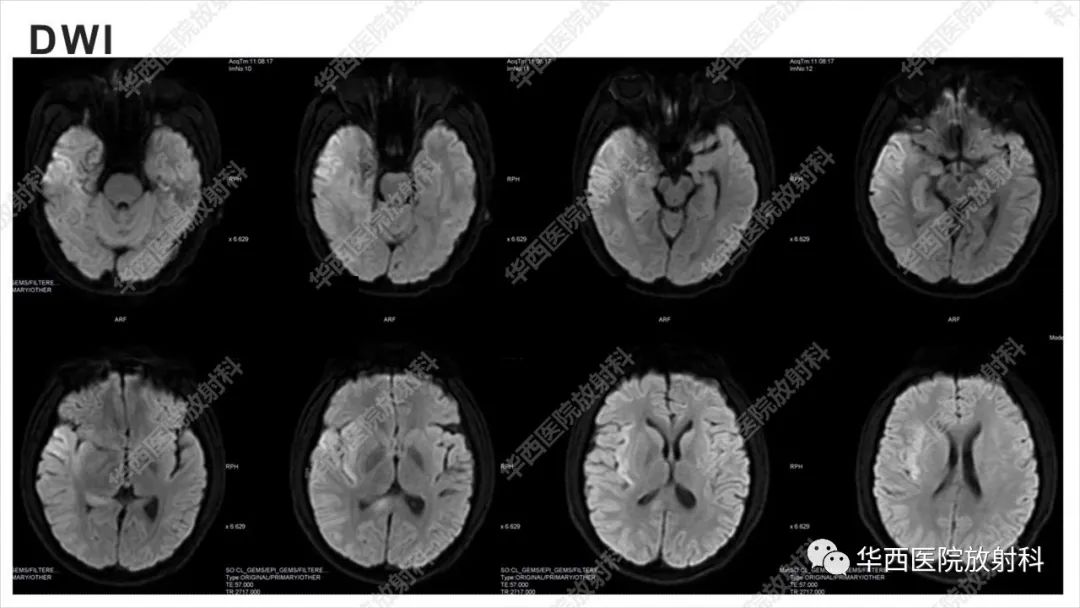

【病例】出血坏死性病毒脑膜脑炎1例CT及MR影像学表现和鉴别诊断-4